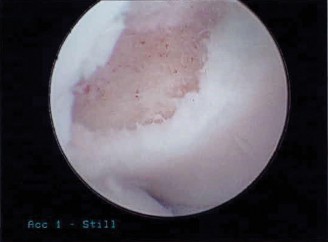

The correct answer is (B). The Snyder classification of SLAP tears is the first widely used classification systems for SLAP tears and consists of types I to IV (see Fig. 2–22A–B and Table 2–3). In type I tears (Answer A), there is fraying of the glenoid edge of the superior labrum, but the biceps tendon and superior labrum are both firmly attached to the biceps anchor and glenoid edge. In type II tears (Answer B), the biceps tendon and the superior labrum are detached from the superior glenoid edge and biceps anchor. In type III tears (Answer C), there is a bucket-handle tear of the superior labrum, but the remainder of the superior labrum and biceps tendon remain firmly attached to the glenoid rim and biceps anchor. In type IV tears (Answer D), there is a bucket-handle tear of the superior labrum that extends into the biceps tendon with extension of parts of the labral flap or biceps tendon into the joint space, and the remainder of the labrum and biceps tendon remain firmly attached to the glenoid rim and biceps anchor. Type V tears (Answer

E) do not exist. Complex lesions do exist and typically consist of a combination of type II and IV tears.

Figure 2–22(A–B) Snyder classification of rotator cuff tears in cartoon and arthroscopic views. (From Mileski RA, Snyder SJ. Superior labral lesions in the shoulder: pathoanatomy and surgical management. J Am Acad Orthop Surg. 1998;6(2):121–131.)